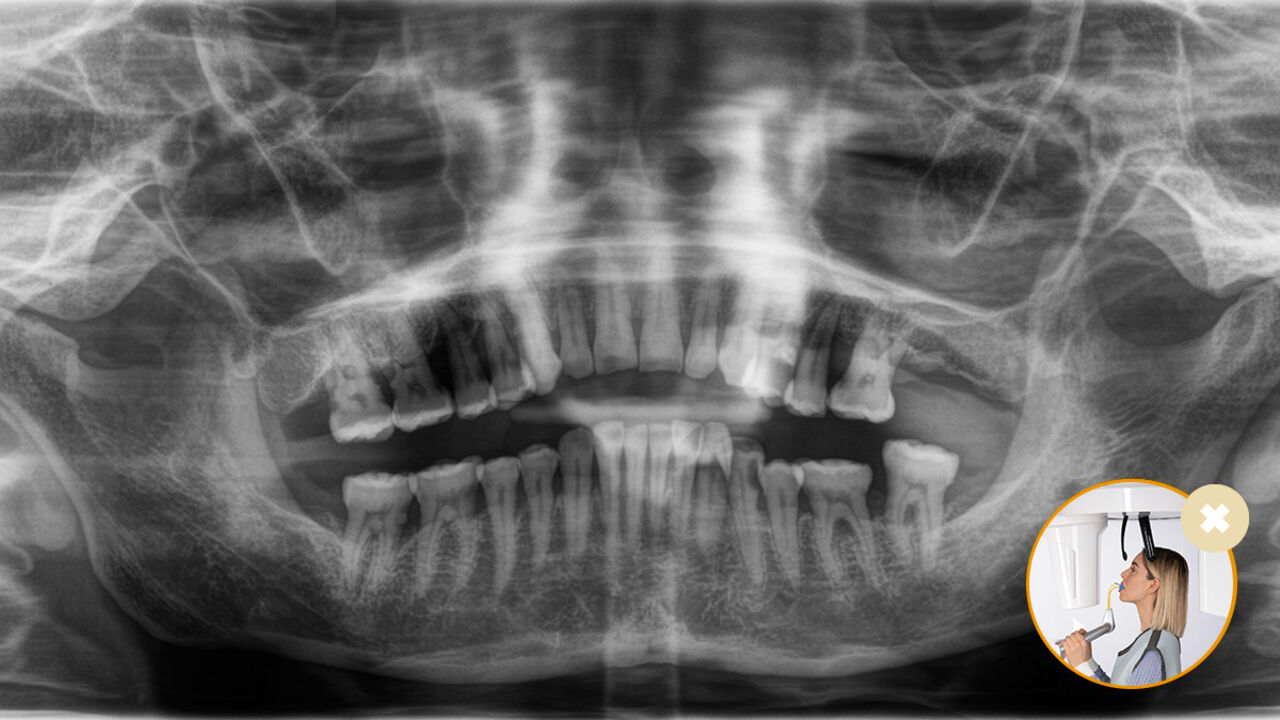

El posicionamiento correcto del paciente permite obtener imágenes de alta calidad que respaldan un diagnóstico preciso y facilitan y mejoran la experiencia del paciente.

Este es nuestro concepto de 10 puntos para facilitar el posicionamiento del paciente y la obtención de imágenes radiológicas. Se trata principalmente de dos cosas: alta calidad de imagen y comodidad para el paciente y el asistente.

Configuración intuitiva a través del EasyPad

El uso del bloque de mordida oclusal no podría ser más sencillo. Con la ayuda de los símbolos y colores en la pantalla del equipo de radiología, los profesionales disponen de toda la información necesaria para un ajuste óptimo del equipo. Las flechas iluminadas indican en qué dirección se debe mover la unidad para lograr la inclinación ideal de la cabeza. El equipo se detiene automáticamente una vez que se alcance la posición correcta.